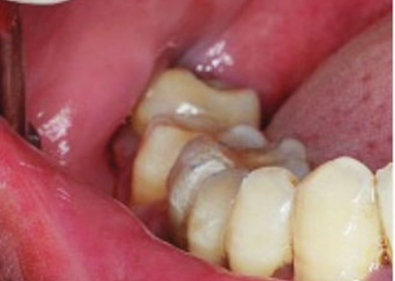

1、智齿冠周炎

由于智齿生长位置不足,因此有部分牙冠被牙龈包围覆盖,在包围牙冠的牙龈与牙齿之间在正常进食后容易藏匿食物残渣,进而引起细菌滋生,导致牙龈红肿发炎,形成智齿冠周炎,严重时化脓形成脓肿,更有甚者向周围肌肉间隙扩散导致面部发炎肿大。